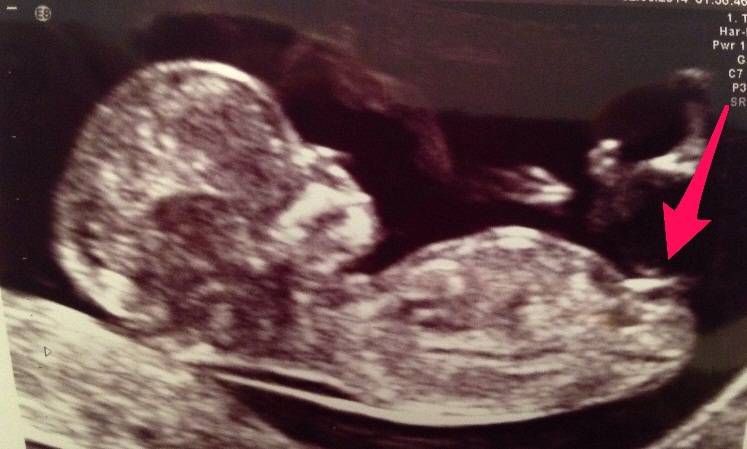

Attachment 16790Attachment 16789I'm new to this nub theory. In fact I don't even know if what the arrow is pointing to is a nub or the cord?? What do you all think? Boy or girl or cord??

Also the heart rate was 135bmp - doesn't that usually indicate boy??